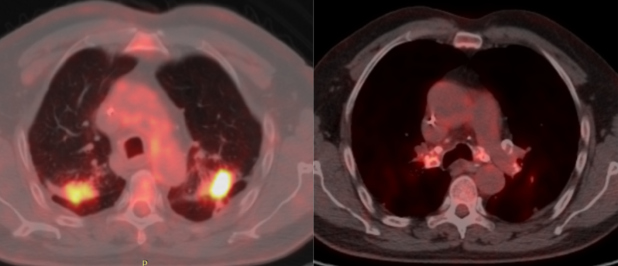

Posterior al tratamiento, se realizó seguimiento con 18F-FDG PET/CT. No se evidenciaron cambios respecto al CT de tórax inicial, pero se registraron hallazgos adicionales de ganglios linfáticos mediastinales hipermetabólicos, con valor estandarizado de captación máximo (SUVmax) entre 3,2 y 5,1, una lesión nodular de bordes irregulares en el segmento posterior del lóbulo superior derecho con SUVmax de 4,4 y otra en el segmento posterior del lóbulo superior izquierdo de 33 x 26 mm con SUVmax de 10,8 que se extiende con tractos fibrosos hacia la pleura, engrosándola (Fig. 2). No se comprobaron lesiones hepáticas y en recto se observó un aumento de captación del trazador de forma lineal, sin engrosamiento ni imágenes sugestivas de recidiva local.

En el caso descrito, se observó en PET/CT ganglios mediastinales y lesiones pulmonares con avidez importante por la FDG, sobre todo en la lesión del lóbulo superior izquierdo con SUVmax de 10,8, lo que hizo sospechar en un principio enfermedad metastásica debido a la patología de base del paciente. Sin embargo, la respuesta completa a la quimioterapia con desaparición de la lesión tumoral primaria y de las metástasis hepáticas, sin cambio alguno en las lesiones pulmonares junto a los antecedentes clínicos, llevó a considerar que las lesiones pulmonares correspondían únicamente a silicosis conglomerada, lo cual fue confirmado por la evolución.